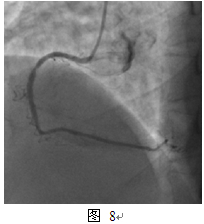

2012年3月发作活动时胸痛,休息可缓解,第一次住我院。入院查体无特殊阳性发现。超声心动图:静息状态下心内结构功能未见异常,LVEF 65%。冠脉造影:右冠支架内再狭窄80%(图8)。同期介入治疗,球囊Fire Star 2.5mm x 15mm预扩,最大14atm,PEB球囊Sequent Please 2.75mm x 15mm, 最大10atm扩张,持续45s(图9)。最终效果满意(图10)。